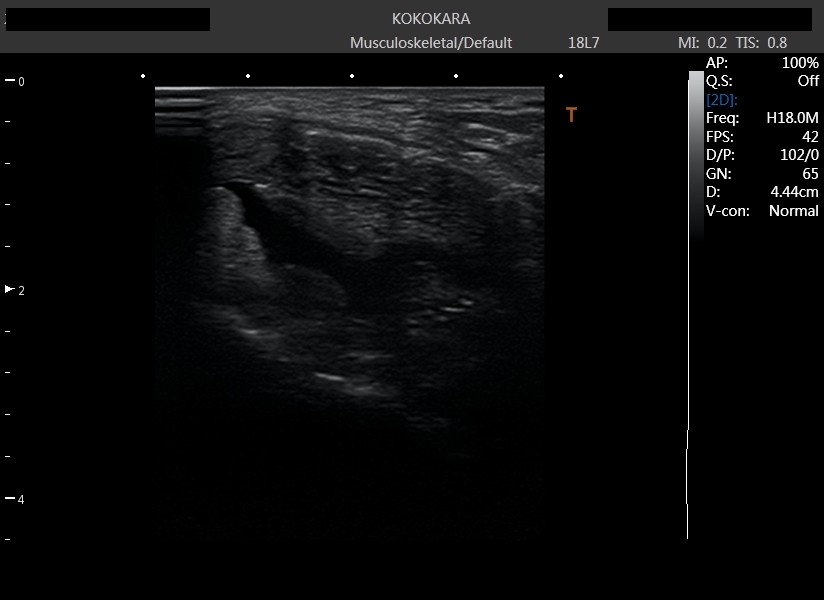

ファシア

ファシアとは

ファシアリリースについて

鍼(はり)2021.07.21

症例報告!膝の痛み

鍼(はり)2020.12.05